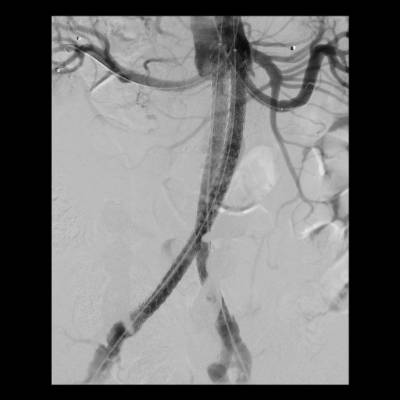

Como ejemplos de este tipo de tratamientos, "en los últimos cinco años se han implantado en el hospital seis endoprótesis ramificadas o fenestradas en pacientes con aneurismas yuxtarrenales o tóraco-abdominales. Además, el Hospital Rey Juan Carlos también realiza la técnica EVAS (Endovascular Aneurysm Sealing) para el sellado de aneurismas abdominales", explica el doctor Tomás Bolivar Gómez

, jefe asociado del Servicio de Angiología y Cirugía Vascular del Hospital Universitario Rey Juan Carlos.

El desarrollo de nuevas técnicas quirúrgicas, prótesis vasculares de última generación, y el abordaje multidisciplinar de estas patologías en colaboración con otros servicios como Cirugía Cardiaca, Cardiología, Radiología Intervencionista, Anestesiología y Medicina Intensiva permite realizar un tratamiento eficaz a un mayor número de pacientes. "La cirugía endovascular posibilita, además, reducir las complicaciones postoperatorias y la estancia hospitalaria, permitiendo el alta habitualmente en 24-48 horas", añade el cirujano vascular.

"Los aneurismas son dilataciones o "globos" en alguna parte de la aorta y su principal problema es que pueden ir creciendo de forma progresiva debilitando la pared de la arteria hasta romperse. Del mismo modo, las disecciones, hematomas intramurales o úlceras penetrantes se originan por una debilidad de la pared de la aorta y pueden provocar su ruptura o bloquear el aporte de sangre a tejidos u órganos vitales, lo que se conoce como isquemia. Cuando estas enfermedades producen una afectación extensa de la aorta, combinando los segmentos torácico y abdominal, o comprometiendo el origen de sus ramas principales, la cirugía vascular ofrece soluciones mediante técnicas endovasculares basadas en catéteres, cirugía abierta convencional o una combinación de ambas", concluye el doctor Tomás Bolívar.